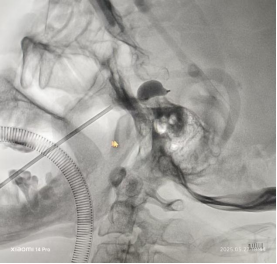

石嗲嗲两年前做过冠状动脉支架植入术,再加上高龄体弱,手术团队完善术前评估后,制定了周密的手术方案。张凌云博士、黄奇武副主任医师和陈珣主治医师仅用30分钟就顺利完成了手术。

张凌云介绍,三叉神经球囊压迫术是一种微创手术,通过在影像引导下将微球囊植入到三叉神经半月节位置,然后向球囊内注入造影剂使其扩张,从而压迫三叉神经的痛觉纤维,达到缓解疼痛的目的。该手术无需开颅,创伤小,患者通常术后当天即可下床活动,观察1-3天即可出院,尤其适用于高龄、身体状况差或无法耐受开颅手术的患者。